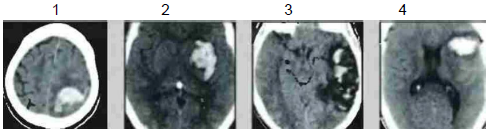

A localização das hemorragias intracranianas varia de acordo com a etiologia.

Associe as imagens 1, 2, 3 e 4 abaixo, relacionando às respectivas causas prováveis.

( ) Uso de cocaína.

( ) Infarto da veia de Labbe.

( ) Malformação arteriovenosa.

( ) Angiopatia amiloide.

A sequência correta dessa associação é: